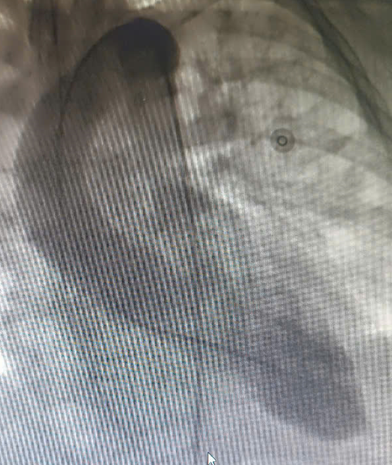

| Trước: Hình chụp tâm thất trái cuối tâm thu. Sau: Cuối tâm trương – giảm động vùng mỏm và tăng co bóp ở vùng đáy - Ảnh BVCC |

Mặc dù chụp mạch vành không phát hiện tổn thương tắc nghẽn, các bác sĩ tiếp tục quyết định chụp hình ảnh buồng tim. Kết quả cho thấy rối loạn vận động điển hình của hội chứng Takotsubo, với tăng co bóp ở đáy và giảm vận động ở mỏm tim, xác định đây là bệnh cơ tim cấp do căng thẳng.